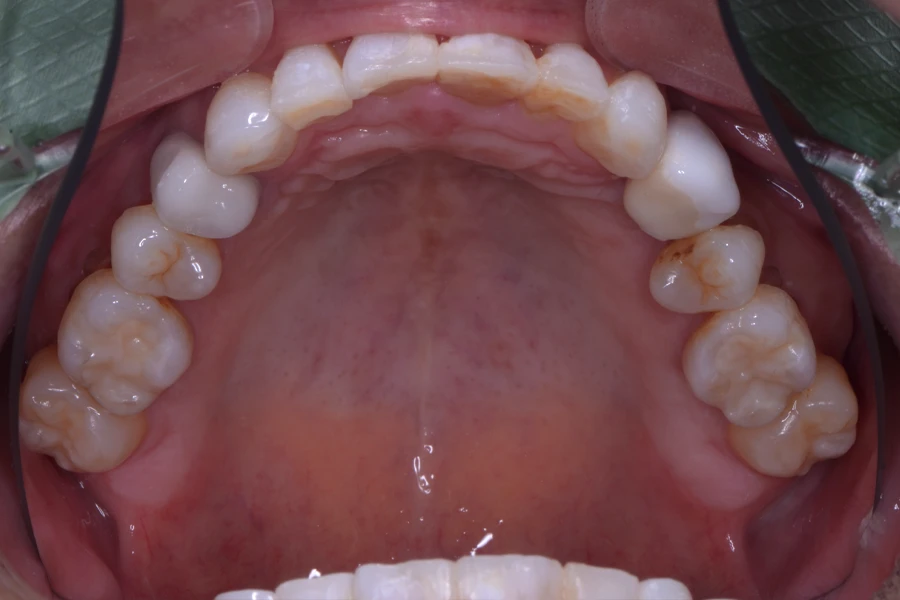

治療後